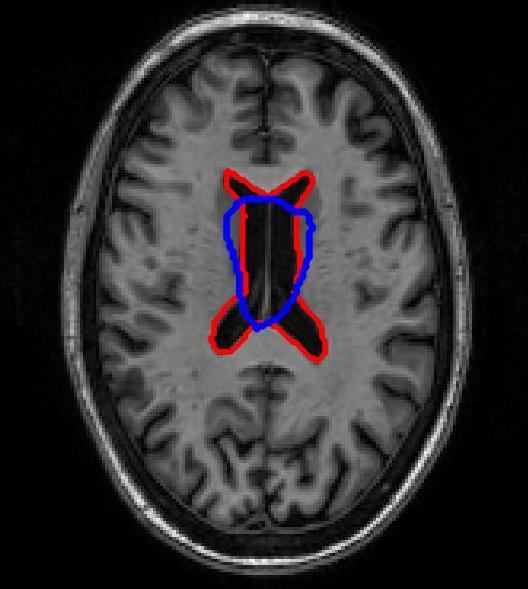

FigureΒ 3 shows results for brain image registration. We show the reference image in FigureΒ 3 (a) followed by an example floating image in FigureΒ 3 (b). The ventricle structure to be aligned is shown in red in both images. FigureΒ 3 (c)-(e) shows the deformed structures obtained by applying the registration field obtained from different methods to the floating image and superimposing these structures on the atlas image. The deformed structures from the floating image are shown in blue. In case of perfect registration the blue and red contours should coincide. In this case SR-Net actually does better than VoxelMorph, while SR-Net does significantly worse due to absence of segmentation information.